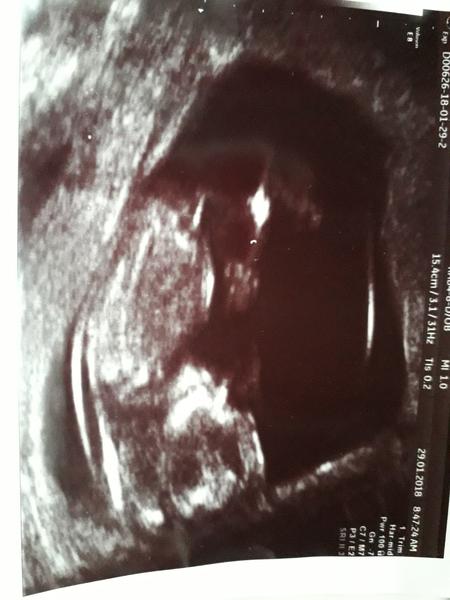

Holky prosim vas a na me fotce je videt hrbolek?

@mikejla_a ja mam podobnou fotecku akorat cernobilou a mame holcicku. Podle sklonu u vas spis chlapecek bych rekla.

@evakaspar myslite,ze jakoby ta "tycinka" je ten hrbolek? Ja si nejsem prave jista..kamoska mela takovou fotku a ma holcicku